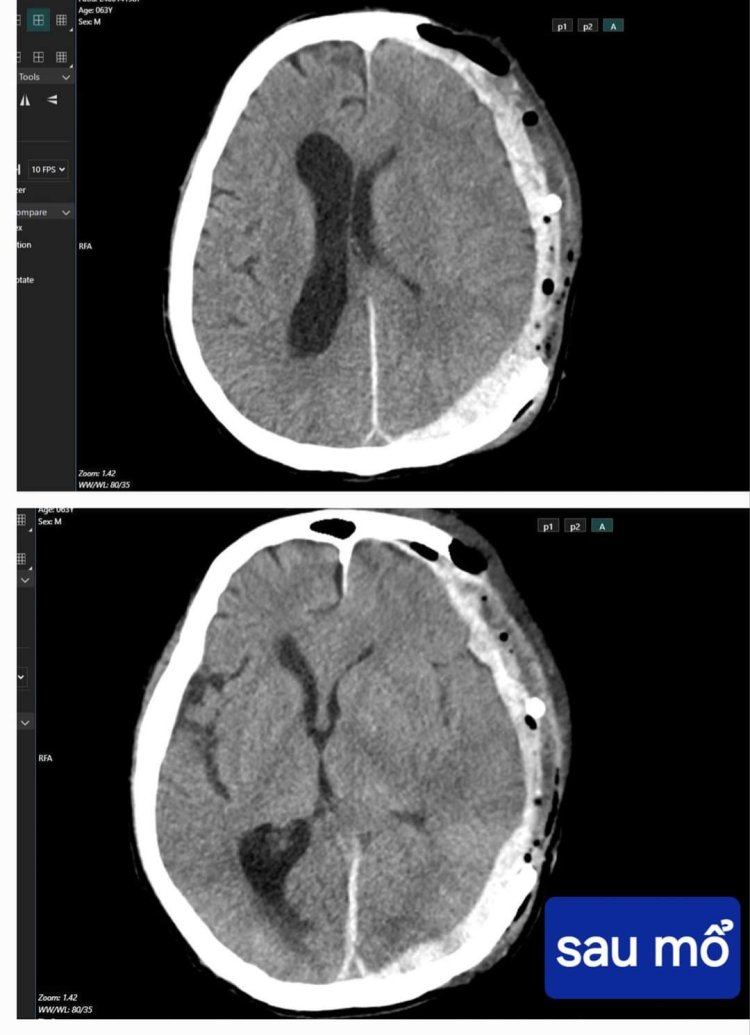

Vừa qua, các bác sĩ Bệnh viện Hữu nghị Việt Nam - Cu Ba Đồng Hới đã phẫu thuật cấp cứu, cứu chữa thành công một bệnh nhân bị chấn thương sọ não nặng GCS 4 điểm, tiên lượng rất nặng.

Lúc vào viện, người bệnh đã hôn mê rất sâu. Đánh giá tình trạng ý thức (GCS) mức 4 điểm. Với mức điểm này, tỷ lệ tử vong sau mổ của bệnh nhân là 95-97%.

Bằng sự tận tâm cứu chữa người bệnh của đội ngũ y bác sĩ Bệnh viện Hữu nghị Việt Nam - Cu Ba Đồng Hới cùng sự may mắn của bệnh nhân, sau mổ, người bệnh phục hồi rất tốt và đã được ra viện sau 10 ngày điều trị. Lúc xuất viện, bệnh nhân trong tình trạng tỉnh táo, không yếu liệt. Đây là một niềm vui to lớn đối với đội ngũ y bác sĩ Bệnh viện và của cả gia đình bệnh nhân.

Người bệnh được xuất viện sau 10 ngày điều trị với tình trạng tỉnh táo, không yếu liệt